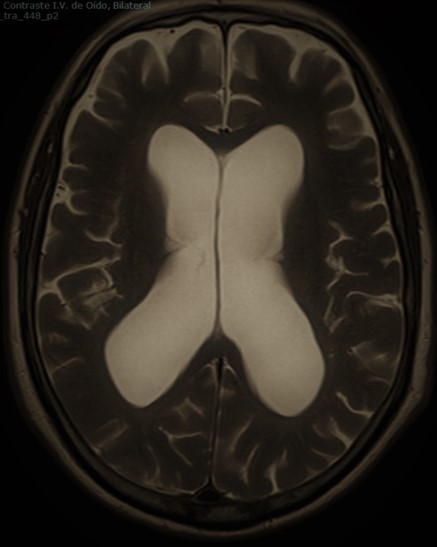

Tratamiento microquirúrgico de tumores cerebrales